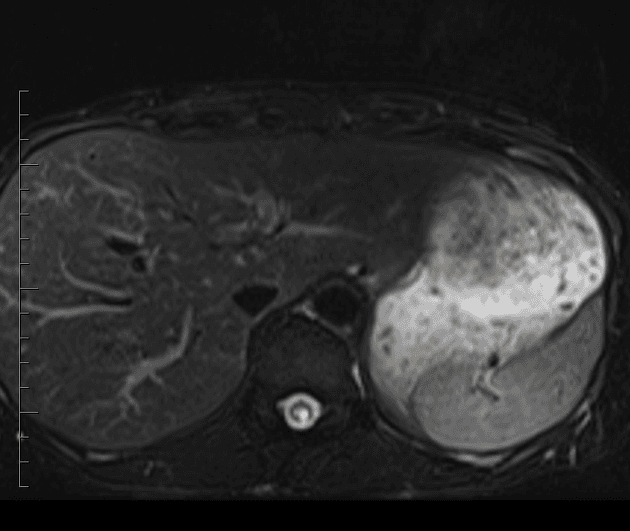

- Cả hai thận đều to ra và chứa nhiều tổn thương nang kích thước khác nhau. Một số nang có thành dày, không đều và ngấm thuốc thì động mạch, hoặc có thành phần đặc lệch tâm ngấm thuốc thì động mạch.

- Một khối tăng tín hiệu trên hình ảnh T2W ở phân đoạn VII gan cũng cho thấy ngấm thuốc sớm dạng nốt ngoại vi và lan tỏa hướng tâm, nghi ngờ u mạch gan (hepatic hemangioma).

- Cả hai thận đều to rõ và đa nang. Một số nang có thành dày lên, gồ ghề, kèm thành phần đặc ngấm thuốc. Ngoài ra, có nhiều ổ vôi hóa nhỏ trong và giữa các nang.

- Một tổn thương giảm tỷ trọng ở gan phân đoạn VII hiện diện, cho thấy ngấm thuốc sớm dạng nốt ngoại vi và ngấm thuốc hướng tâm (centripetal filling), phù hợp nhất với u mạch gan (hepatic hemangioma).

- Các hình ảnh trên MRI và CT theo dõi phù hợp với bệnh Von Hippel-Lindau, đặc trưng bởi sự phát triển của nhiều khối u lành tính và ác tính ở các cơ quan khác nhau, đặc biệt là thận, tuyến thượng thận, tụy, gan và hệ thần kinh trung ương (CNS).

Bệnh Von Hippel-Lindau (VHL) là một hội chứng hiếm di truyền trội trên nhiễm sắc thể thường, do đột biến gen ức chế khối u VHL trên nhiễm sắc thể 3p. Bệnh làm tăng nguy cơ phát triển nhiều khối u lành tính và ác tính, đặc biệt ở hệ thần kinh trung ương (u mạch máu dạng tế bào khổng lồ), thận (ung thư biểu mô tế bào ống thận loại tế bào sáng), tụy (u tuyến nang tuyến, u thần kinh nội tiết), tuyến thượng thận (u tế bào ưa crôm) và cơ quan sinh sản (u tuyến mào tinh). Các hình ảnh học trong trường hợp này — thận đa nang hai bên với thành phần đặc ngấm thuốc, u thần kinh nội tiết tụy và u mạch gan — là những biểu hiện điển hình của VHL. Việc phát hiện sớm thông qua theo dõi định kỳ bằng MRI và CT rất quan trọng vì ung thư biểu mô tế bào thận là nguyên nhân tử vong hàng đầu. Xét nghiệm di truyền và tầm soát cho các thành viên trong gia đình được khuyến nghị ở những người có nguy cơ.